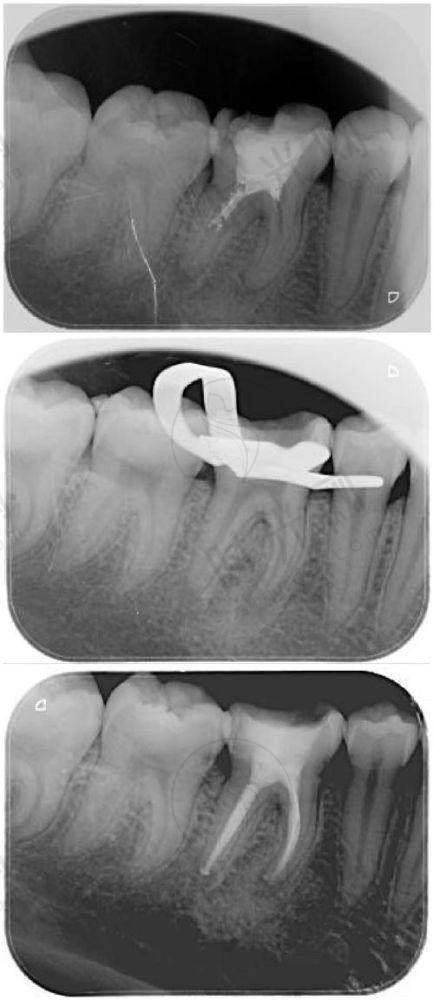

补牙(树脂填充):国产树脂140 - 600元/颗,进口3M树脂300 - 800元/颗。注意!浅龋(表层蛀牙)补牙医疗保险报销后自费低至70元,但如果蛀牙烂到神经(牙髓炎),需做根管治疗,费用立刻涨到800 - 2000元/颗(医疗保险报销后约400 - 1000元)。